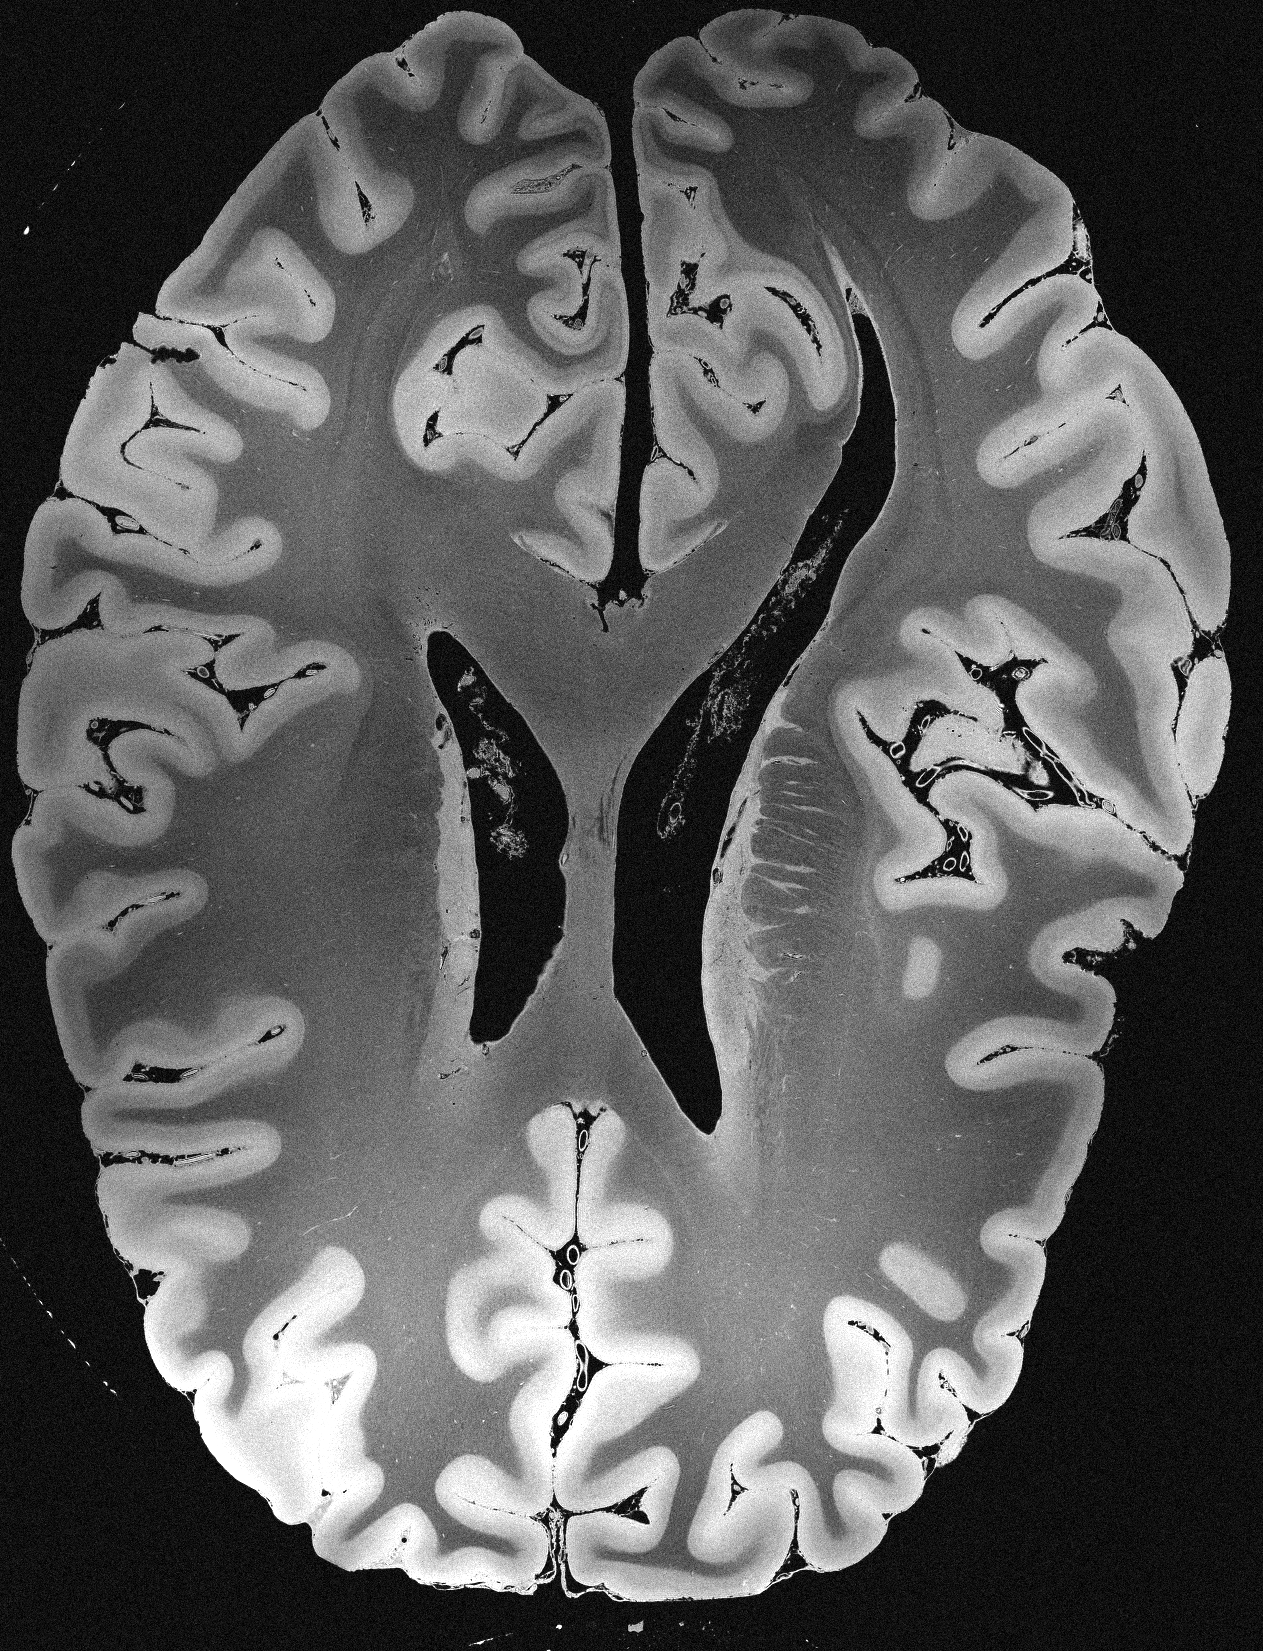

4.2 Registration to a 100 micron ex-vivo brain MRI volume

To showcase the efficacy of our method on real large scale images, we register a 250 in-vivo MRI image (Lüsebrink et al., 2017) to a 100 ex-vivo FLASH human brain volume (Edlow et al., 2019). This represents an inverse problem with more than 11.2B optimizable parameters (compared to 20M for clinical datasets), or 44.8GB of GPU memory. The entire problem does not fit on most GPUs, necessitating distributed multimodal registration. We optimize a composite transform - affine followed by a diffeomorphic mapping; details can be found in Section E.1. Multimodal deformable registration took 58 seconds on 8 NVIDIA A6000 GPUs, which is unprecedented at this resolution. Fig. 6 shows qualitative results, highlighting the ability to register highly detailed structures such as cerebellar white matter; these structures are not visible at macroscopic scales. The resultant advantages of performing registration at this scale can allow researchers to characterize the neuroanatomy at microscopic resolutions and allow morphometric analysis of cortical layers and subcortical nuclei among other structures.